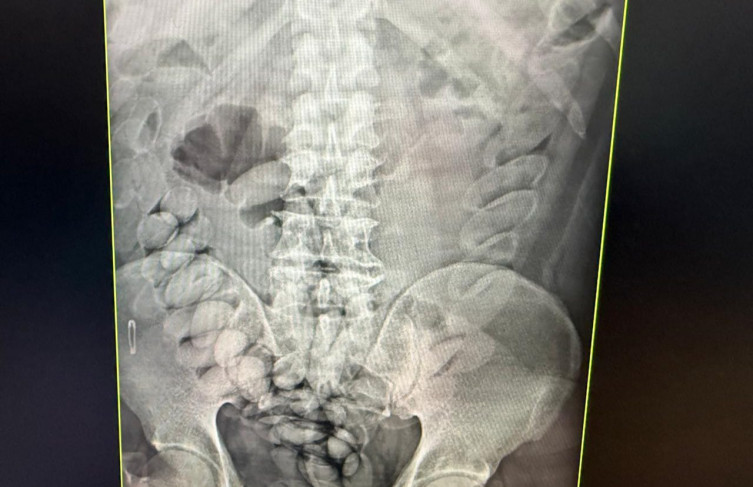

Exames de raio-x comprovaram a ingestão de entorpecente

Durante a fiscalização, os agentes localizaram, no banheiro do ônibus, cápsulas de pasta base de cocaína. Com o auxílio de um cão farejador, suspeitos foram abordados, o que levou à identificação de três passageiros de nacionalidade boliviana como possíveis responsáveis pelo transporte da droga.

Os indivíduos foram encaminhados ao hospital, onde exames confirmaram que haviam ingerido cápsulas com o entorpecente. Após expelirem a droga, eles foram levados à Polícia Federal para prestar depoimento e, em seguida, foram presos. Ao todo, cerca de 4 quilos da droga foram apreendidos.